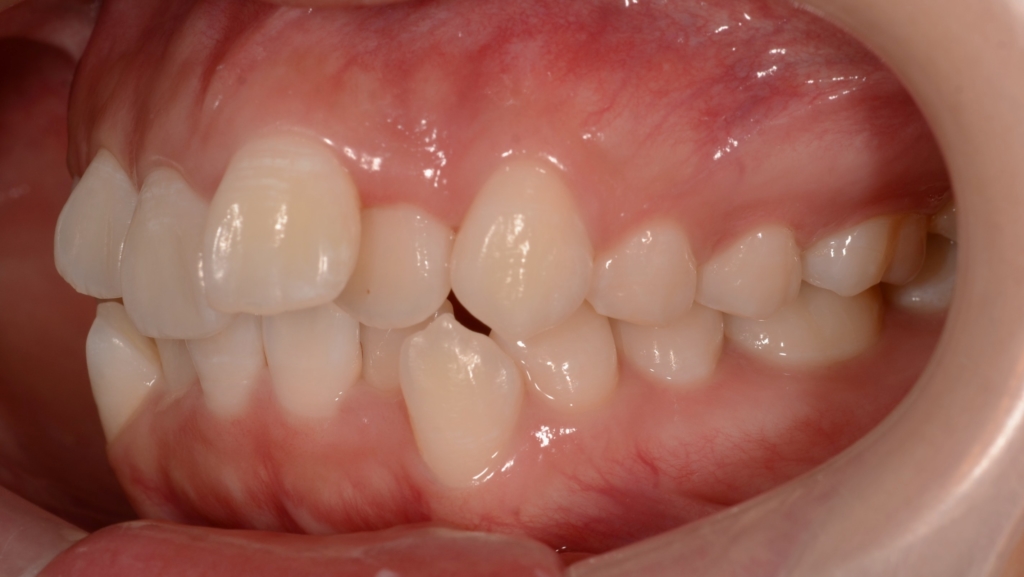

出っ歯とデコボコを治したい

#1.(歯列の前方位による)上顎前突

#2.歯と顎の不調和による叢生(中等度)

【治療方針】

1.上下の左右の奥歯を1本ずつ(計4本)抜歯をしてスペースを作り、

上下の前歯をきれいに並べる

2.次いで、残る隙間分、前歯を最大限に後方へ引っ込める